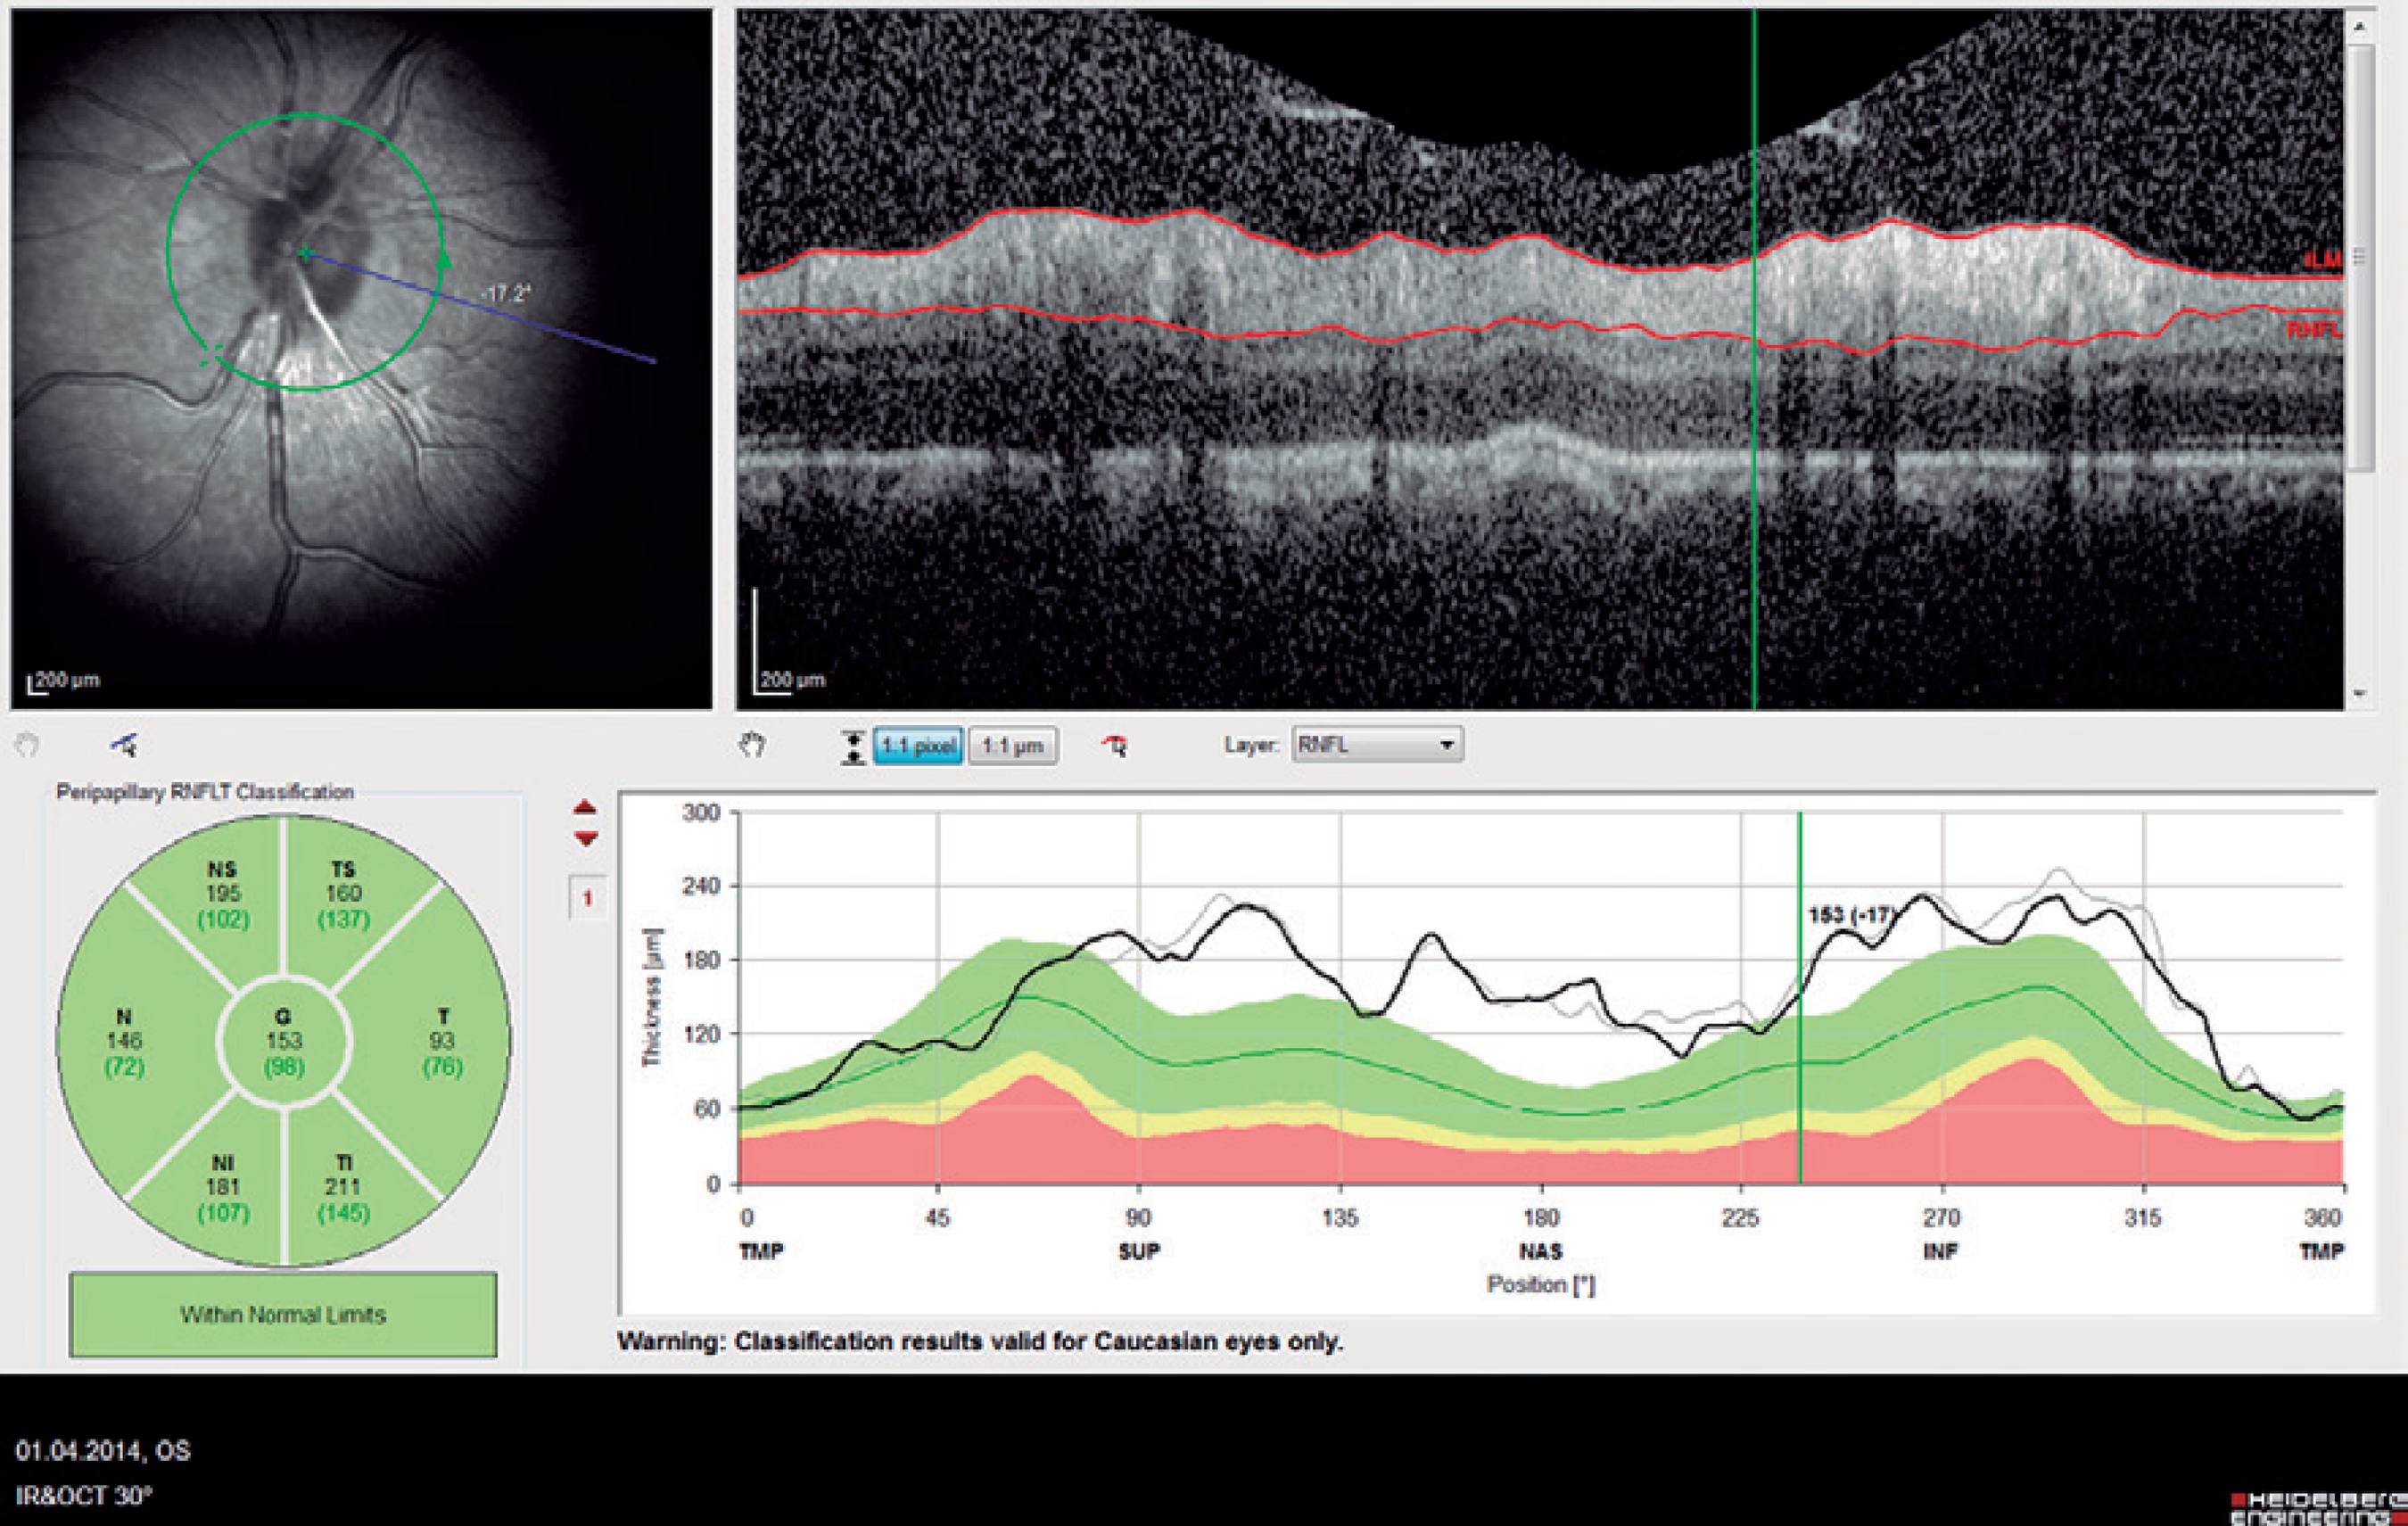

The central macular thickness (CMT), RNFL thicknesses, and choroidal thickness (CT) measurements were obtained using the Spectralis SD-OCT (Heidelberg Engineering; wavelength: 870 nm) with the enhanced depth imaging modality that has previously been described) (Figure 1)(16). All subjects were imaged by the same experienced technician. The central subfoveal choroidal thickness (CSCT), temporal choroidal thickness (TCT; 1 mm temporal CT from the fovea), and nasal choroidal thickness (NCT; 1 mm nasal CT from the fovea) were measured by two clinicians (I.Y. and E.P.) in a blinded manner, without knowledge of information of the subjects, and the mean of their measurements was used in the analysis. Measurements with a difference larger than 10% between the clinicians were excluded from the study. The peripapillary RNFL thickness parameters were automatically calculated using the same SD-OCT device and divided into regions including nasal (N) quadrant thickness (90º), nasal superior (Ns) quadrant thickness (45º), nasal inferior (Ni) quadrant thickness (45º), temporal (T) quadrant thickness (90º), temporal superior (Ts) quadrant thickness (45º), temporal inferior (Ti) quadrant thickness (45º), and mean (G) thickness (360º) (Figure 2). To minimize the possibility of choroidal changes attributable to diurnal choroidal fluctuations(17), all scans were performed during the same time of the day between 11:00 a.m.-12:00 p.m.